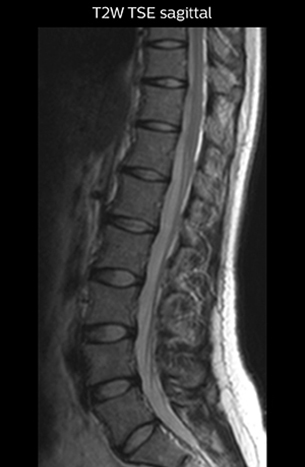

“For example, in sagittal images, when the presence of fat is observed in the intervertebral foramen, it suggests that there is a margin around the nerve. Similarly, the absence of fat indicates that the nerve is being compressed. So, we used to deduce nerve compression indirectly. With NerveVIEW, however, we can observe the condition of the nerves directly, regardless of the presence or absence of fat. We always prefer such direct observation of anatomy over having to make an inference about it.”

“Although symptoms of typical disc herniation and atypical hernia are very similar, the actual site of herniation is different. It is therefore important to characterize the nerve’s condition both inside and outside of the intervertebral foramina. “Conversely, if we see no abnormality in NerveVIEW, we can assume at least that there is no severe condition that requires surgery. Like this, it can help us avoid unnecessary surgery. NerveVIEW can have a tremendous impact in this way.”

“NerveVIEW is really useful for those cases where a nerve disorder is strongly suspected based on the clinical examination but our regular MRI images do not show any findings. These atypical herniations and spinal canal stenosis, occurring in 5% to 15% of the total lumbar herniation/stenosis cases are our main target when using NerveVIEW,” says Dr. Yabuki.

Implementing NerveVIEW without lengthening exam time “The source images of NerveVIEW exhibit a contrast similar to STIR or fat-suppressed T2-weighted images. So, in our neurography exams we are replacing the 2D T2-weighted coronal sequence with 3D NerveVIEW. With this, we add a lot of useful information without adding scan time. This is important for patients with severe lower extremity symptoms, as they often find it difficult to maintain still during the whole MRI examination, so the exam should be as short as possible.” “We have currently implemented 3D NerveVIEW on our Achieva 3.0T dStream MRI system only. Because the 3D NerveVIEW method is based on a background signal suppression technique, we decided to use the high SNR of our 3.0T MRI system for obtaining the best possible visualization of peripheral nerves,” says Tanji. “Where NerveVIEW of the lumbar plexus is currently used as a subroutine scan for patients with strong lower limb symptoms, its use for visualization of the brachial plexus, is currently limited to special cases such as schwannomas and neuritis, usually only 1 or 2 cases per month.”